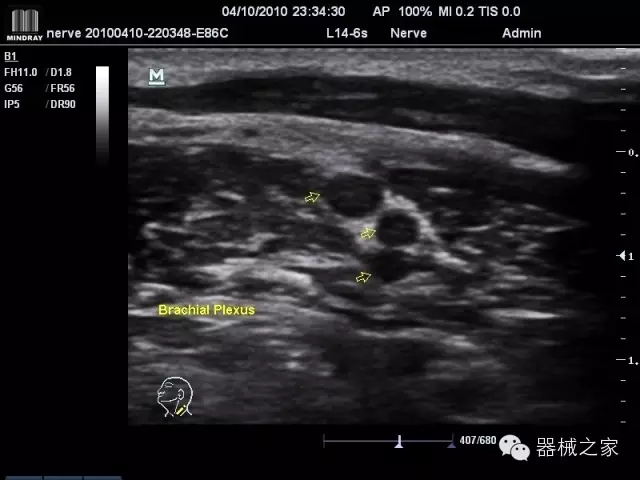

臨床圖片賞析

產(chǎn)品特點(diǎn)

·裝載有采用Multi-Core多核處理的非嵌入式平臺,成像效率大大提高,并且能夠給用戶帶來高速、多任務(wù)并行信號處理體驗(yàn);

·優(yōu)秀的圖像效果、強(qiáng)大的功能體驗(yàn)、豐富的探頭選擇、合理的便攜式設(shè)計(jì),全中文顯示及病人管理界面,使得M7在任何場合、任何時(shí)候都能快速響應(yīng)更好的心血管、腹部、婦產(chǎn)、小器官等常規(guī)超聲檢查以及肌骨、神經(jīng)、顱腦、術(shù)中等新興領(lǐng)域的使用需求;

8倍波束并行處理系統(tǒng)

·在便攜式緊湊平臺上采用更多倍波束并行接收信號處理模式,無論二維還是彩色血流圖像狀態(tài)下,擁有更靈敏的回波頻移捕獲能力,大大提高時(shí)間分辨率,尤其使得心血管表現(xiàn)更為突出;

PSHI?寬帶頻移諧波技術(shù)

·在普通組織諧波的基礎(chǔ)上,通過精確控制的波束形成器,發(fā)射兩組具有相位偏差反向的信號,并采用并行信號處理,數(shù)字化合成并采樣回波信號,在高靈敏度的濾波器的處理過程中獲取更純凈的諧波信號,使圖像具有更加出眾的細(xì)節(jié)分辨率;

iClear®+iBeam?

·智能化按線復(fù)合多角度獲取聲束的原始信號,配合智能化的斑點(diǎn)噪聲識別及控制處理技術(shù),整體提高組織結(jié)構(gòu)細(xì)節(jié)分辨率,任何時(shí)候都能快速響應(yīng),更好的滿足心血管的使用需求;

支持全新3T工藝探頭群

·包括探頭材料、結(jié)構(gòu)設(shè)計(jì)、加工工藝三方面的革新技術(shù)給圖像帶來品質(zhì)的飛躍;